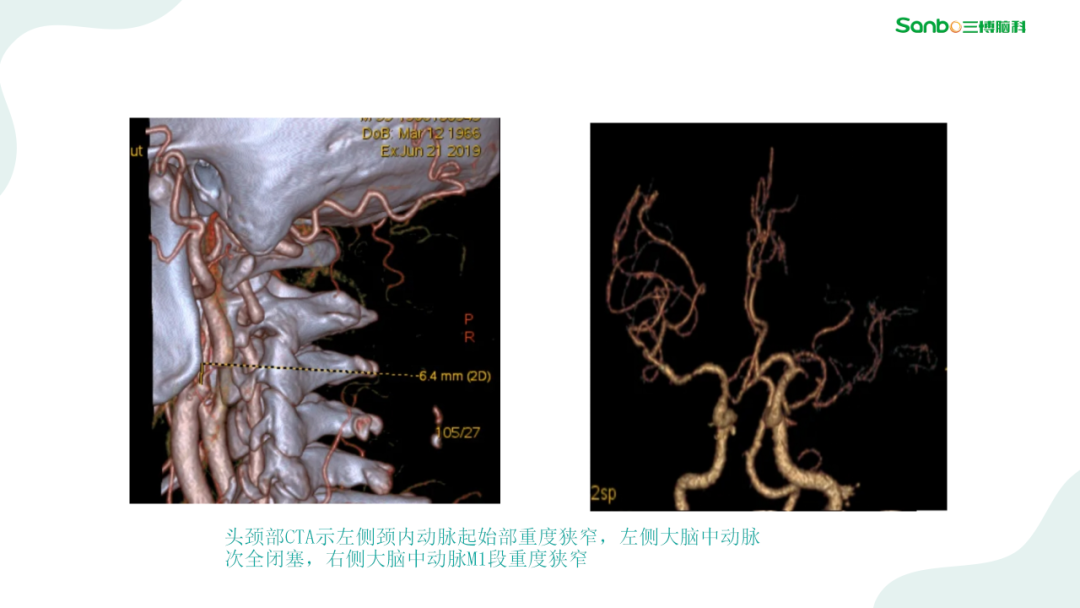

2月28日下午3:00,第二期“健康小课堂”科普活动由神外二科副主任杨海洋围绕《脑血管病的那些事》,给大家耐心讲解了有关脑血管的相关知识,生动的讲课引发在场的热烈讨论,大家纷纷表示受益匪浅。